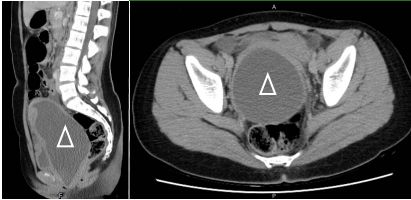

99 15 歲的女性沒有過去病史,尚未來月經,第二性徵發育正常,排便、解尿無異常,這一星期以來感 到一陣陣下腹悶痛,疼痛指數高達 8 分,休息吃止痛藥都無法緩解,越來越痛,沒有發燒或噁心嘔 吐的現象。來急診時,腹部電腦斷層及身體檢查結果如下圖,圖中的病灶(∆)位於子宮,關於她腹 痛的原因,下列敘述何者最不適當? (A)為原發性無月經症(primary amenorrhea) (B)可能合併骨骼及泌尿系統異常 (C)可能是雄性激素失敏症(androgen insensitivity) (D)腹痛原因是子宮內積血(hematometra)或陰道內積血(hematocolpos)